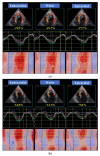

The endomyocardial form of restrictive cardiomyopathy (EMF-RCM), a primary disorder of the myocardium, is one of the diseases with poor prognosis in cats. We hypothesized that both the left and right myocardial functional abnormalities may occur in cats with EMF-RCM, causing this disease pathophysiology and clinical status. Out of the 25 animals included in this study, 10 were client-owned cats with EMF-RCM, and 15 were healthy cats. In this study, cats were assessed for layer-specific myocardial function (whole, endocardial, and epicardial) in the left ventricular longitudinal and circumferential directions, and right ventricular longitudinal direction, via two-dimensional speckle-tracking echocardiography (2D-STE). Cats with EMF-RCM had depressed left ventricular myocardial deformations both in systole (whole longitudinal strain, epicardial longitudinal strain, and endocardial circumferential strain) and diastole (early and late diastolic longitudinal strain rates, and late diastolic circumferential strain rate) compared to controls. Furthermore, some right ventricular myocardial deformations (systolic longitudinal strain in epicardial layers, and endocardial-to-epicardial strain ratio) were significantly differerent in cats with EMF-RCM. Myocardial function assessed by 2D-STE could reveal left and right myocardial dysfunction.